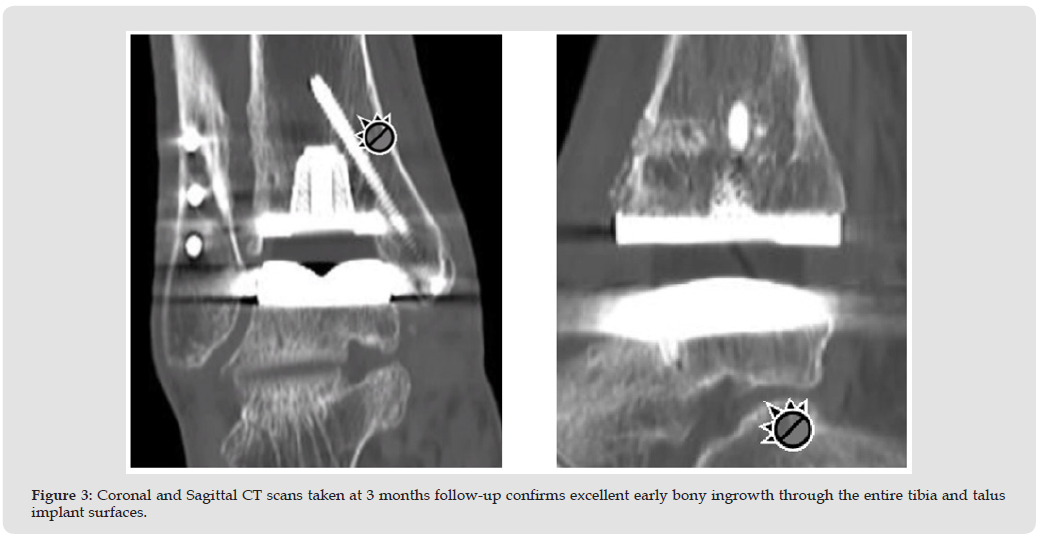

The patient is a 66-year-old female (BMI-24) presenting with disabling pain due to post-traumatic ankle arthritis from an ankle fracture and repair surgery which occurred 30 years earlier. The pain has progressed over the years to the point where the patient is no longer able to perform ADLs. Her right ankle alignment is normal. Past surgical incisions both lateral and medial are well healed. There is tenderness of the anterior ankle joint line, with limited ROM 5 degrees dorsiflexion and 10 degrees plantarflexion. She exhibits an antalgic gait (pain causing pronounced limp) despite no ankle instability. Past medical history includes hypertension and hypothyroidism. It was determined that surgery would be necessary for symptom relief and the patient was a suitable candidate for TAR (Figure 1). The surgery consisted of removal of previous hardware from the tibia and prophylactic fixation of the medial malleolus, then implantation of a modern generation style TAR (Paragon 28 Apex3D, Biomet Inc. Warsaw, IN). Catalyst Bone Graft (approximately 2 cc’s) was applied as a bone void filler to the ingrowth/ongrowth surfaces to improve bony incorporation and healing (Figures 2a & 2b). At three months follow-up the patient progresses clinically as expected with physical therapy, and both coronal and sagittal CT scans show excellent bony ingrowth through and around the entire tibia and talus implant surfaces (Figure 3).